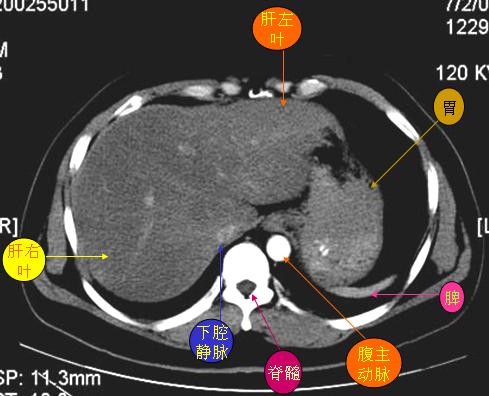

腹部ct解剖与基本病变